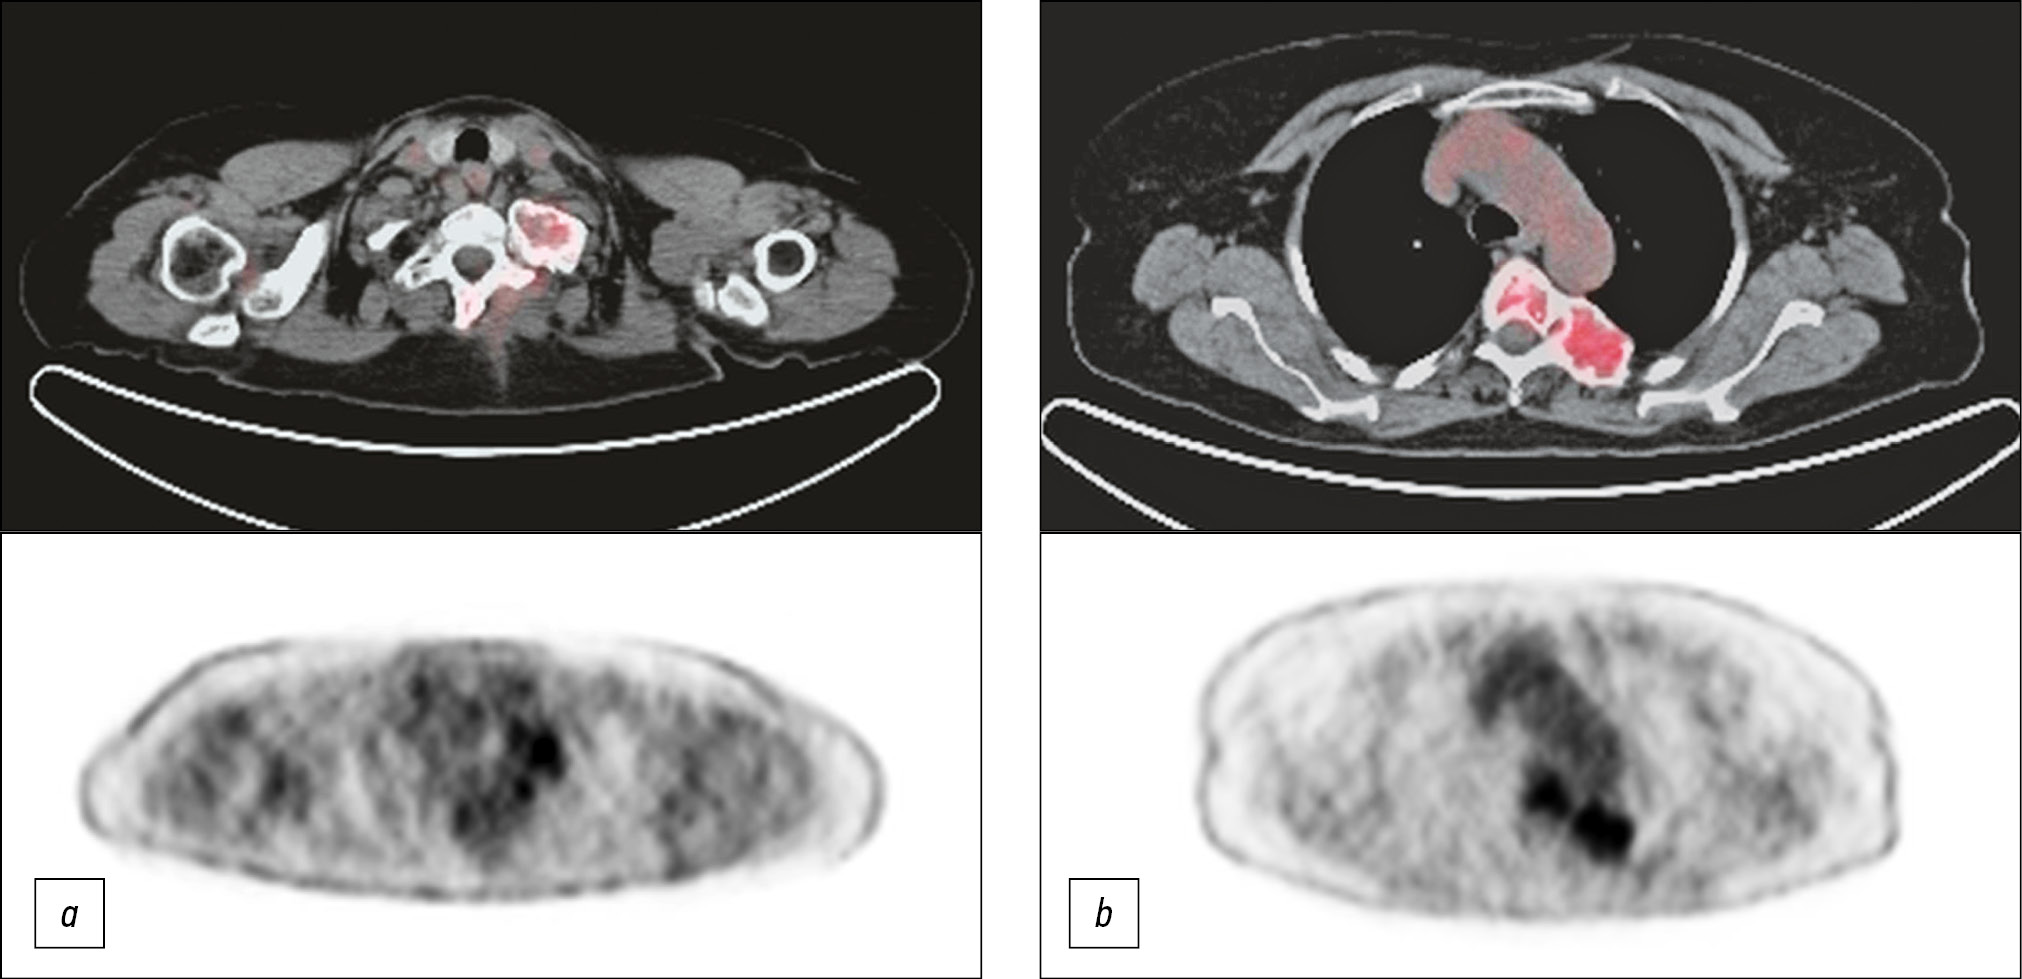

The whole body Fluorine-18 Fluorodeoxyglucose PET-CT scan confirmed the involvement of each of the above-mentioned skeletal segments and identified with other imaging methods but, paying special attention to some of them that showed more intense uptake of the radiotracer, specifically the posterior arch of the first left rib, the fifth vertebral body, and the left posterior arch of the corresponding rib (Fig. 4).

Fig. 4. 18F-FDG PET-CT scan showing an increased tracer uptake at the posterior arch of the first left rib (4a), the fifth dorsal vertebra, and the posterior arch of the corresponding left rib (4b).